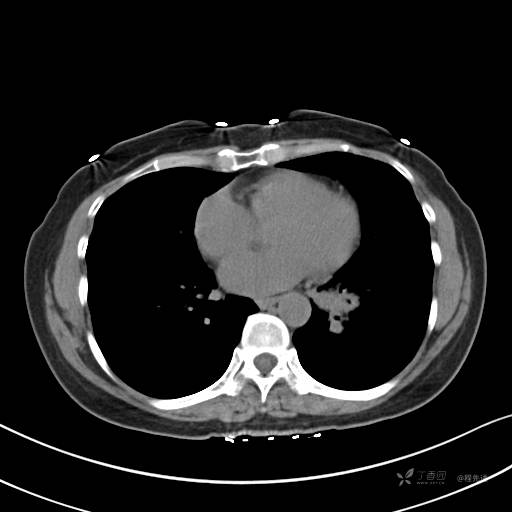

CT平扫

纵隔窗

病灶平扫CT值约31HU